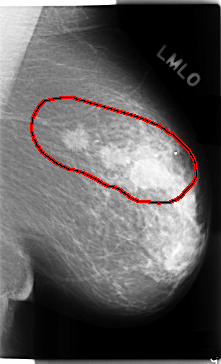

FILE: C_0112_1.LEFT_MLO.OVERLAY

TOTAL_ABNORMALITIES 1

ABNORMALITY 1

LESION_TYPE MASS SHAPE IRREGULAR MARGINS SPICULATED

ASSESSMENT 5

SUBTLETY 5

PATHOLOGY MALIGNANT

TOTAL_OUTLINES 1

BOUNDARY